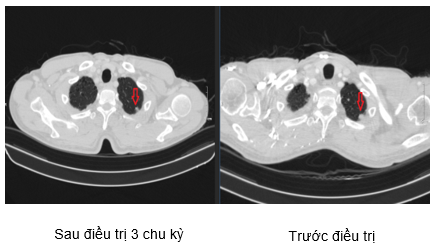

Hình 4. Hình ảnh khối u gan sau 3 chu kỳ điều trị: các khối u lớn nhất đường kính 22mm (hình bên trái) đã giảm kích thước so với phim trước điều trị (hình bên phải).